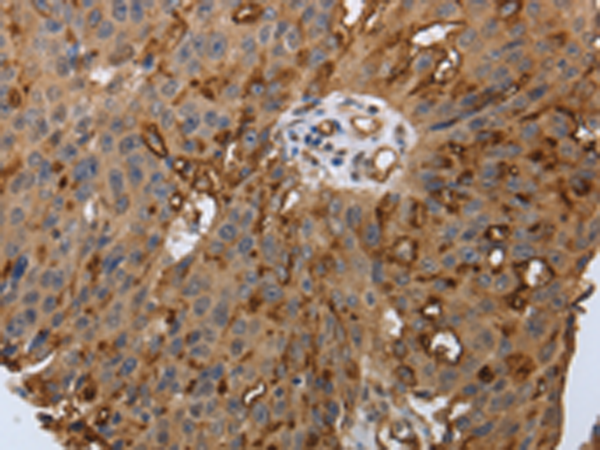

分类: 科研抗体货号: P11337别名: PN3; SNS; hPN3; Nav1.8应用: IHC反应种属: Human